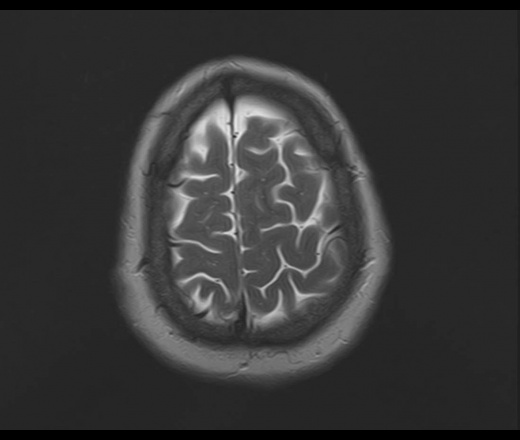

У пациентки 1960 г.р. с 2005 наблюдается птоз, диагноз миастении исключен. МРТ ГМ впервые выполнено в августе 2015 г в плановом порядке, новых жалоб не было, по описанию МРТ - очаговые изменения белого и серого вещества больших полушарий и ствола мозга - признаки энцефаломиелита.

В сентябре 2015 новое МРТ: субкортикальные очаги в белом веществе больших полушарий, не накапливающие контраст; уменьшение размеров ряда очагов - Данных за демиелинизирующее заболевание нет, поствоспалительные изменения. Консультирована в НИИ неврологии, предположено демиелинизирующее заболевание вторичного генеза. В неврологическом статусе: правосторонний птоз, ограничение конвергенции, асимметрия носогубных складок.

Сейчас вновь сделано МРТ, появлись 2 новых очага: в полюсе правой височной доли и поперечной височной извилине слева. Очаг в задних отделах левой теменной доли (угловая извилина) увеличился в размерах. С контрастом пока не работаем.

Подскажите, пожалуйста, что это за процесс? Поражено только белое вещество или серое также? Есть ли поражение ствола мозга?

Действительно, динамика отрицательная и на первичную демиелинизацию не тянет. Какой-то продолжающийся энцефалит, какой именно и гадать нечего, это не наше дело, навскидку можно написать длинный ряд типа Эбштейна-Барра и пр, всё требует серологического доказательства.. В стволе ничего не увидел. Поражено белое и серое вещество.